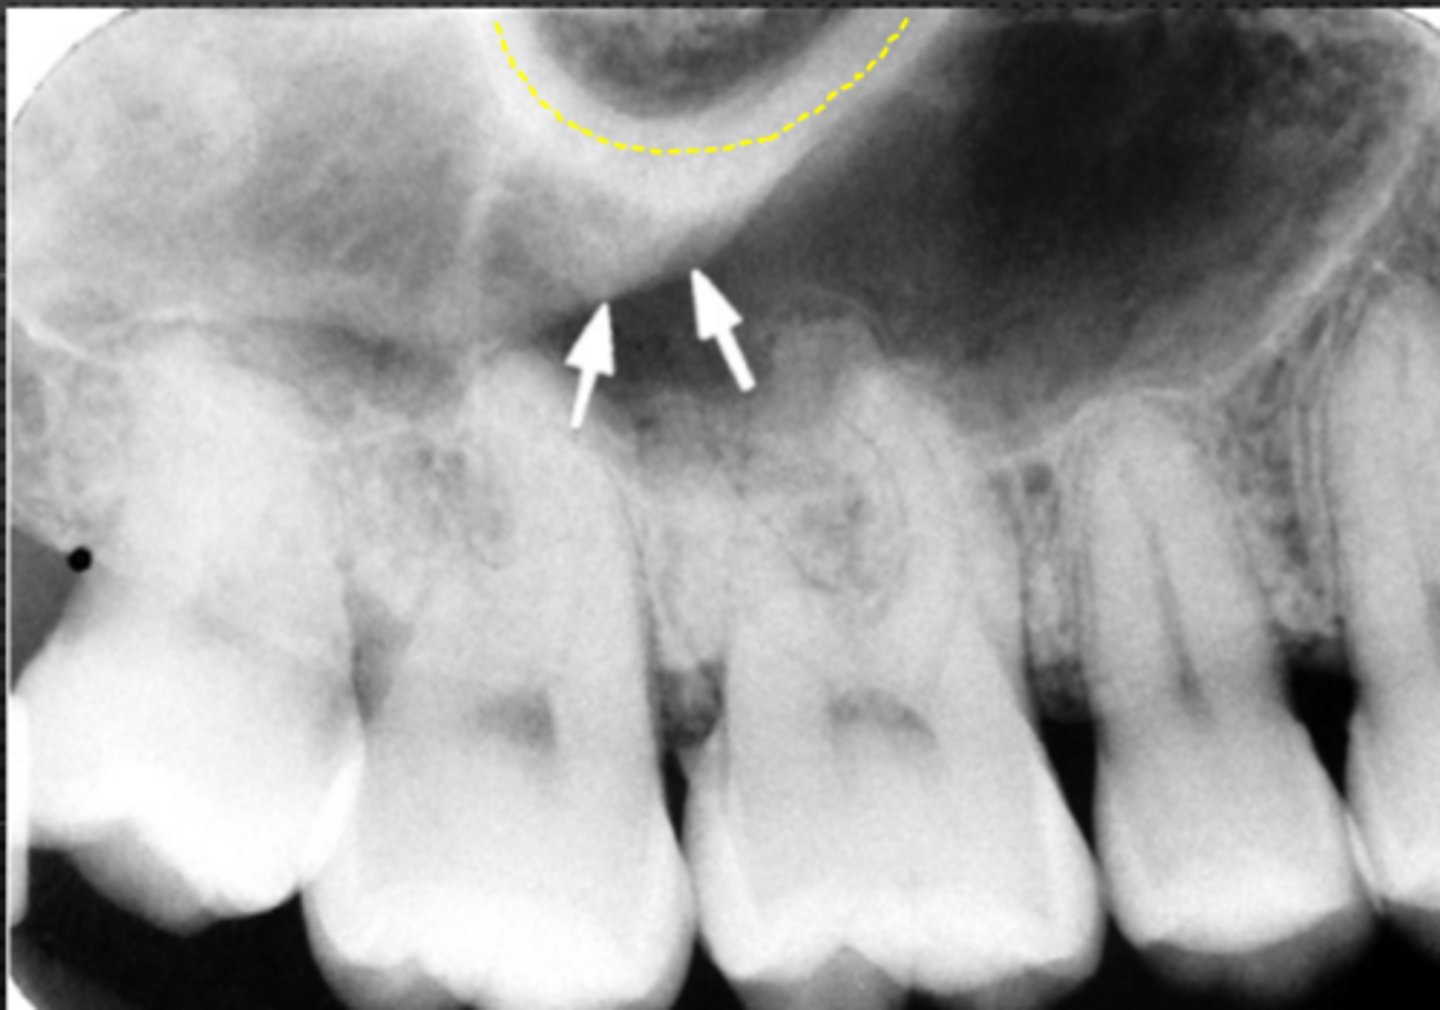

50

New cards

Sinus septum

Name the straight (slightly curved), radiopaque structure indicated by the arrows.

<p>Name the straight (slightly curved), radiopaque structure indicated by the arrows.</p>